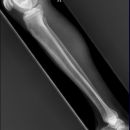

Unterschenkel a.p. und seitlich

Normalerweise ergeben sich bei Unterschenkelschaftfrakturen keine größeren diagnostischen Probleme. Aufnahmen in zwei Ebenen sind normalerweise ausreichend. In der Regel frakturieren Tibia und Fibula gemeinsam: „komplette Unterschenkelschaftfraktur“.

Zur sicheren Abschätzung von Rotationsfehlstellungen sollte immer der ganze Unterschenkel mit angrenzenden Gelenken abgebildet sein!

Isolierte Fibulafrakturen sind selten! Auch bei hohen Fibulafrakturen unbedingt nach primären Verletzungen des OSG fanden! Maisonneuve-Fraktur!

Bei Kindern auf Epiphysenfugenverletzungen achten Achsgerechte Stellung der Epiphyse in beiden Ebenen? Weite der Fugen (normalerweise 3-6mm)? evtl. Gegenseite zum Vergleich röntgen!

AO-Klassifikation der Unterschenkelfrakturen